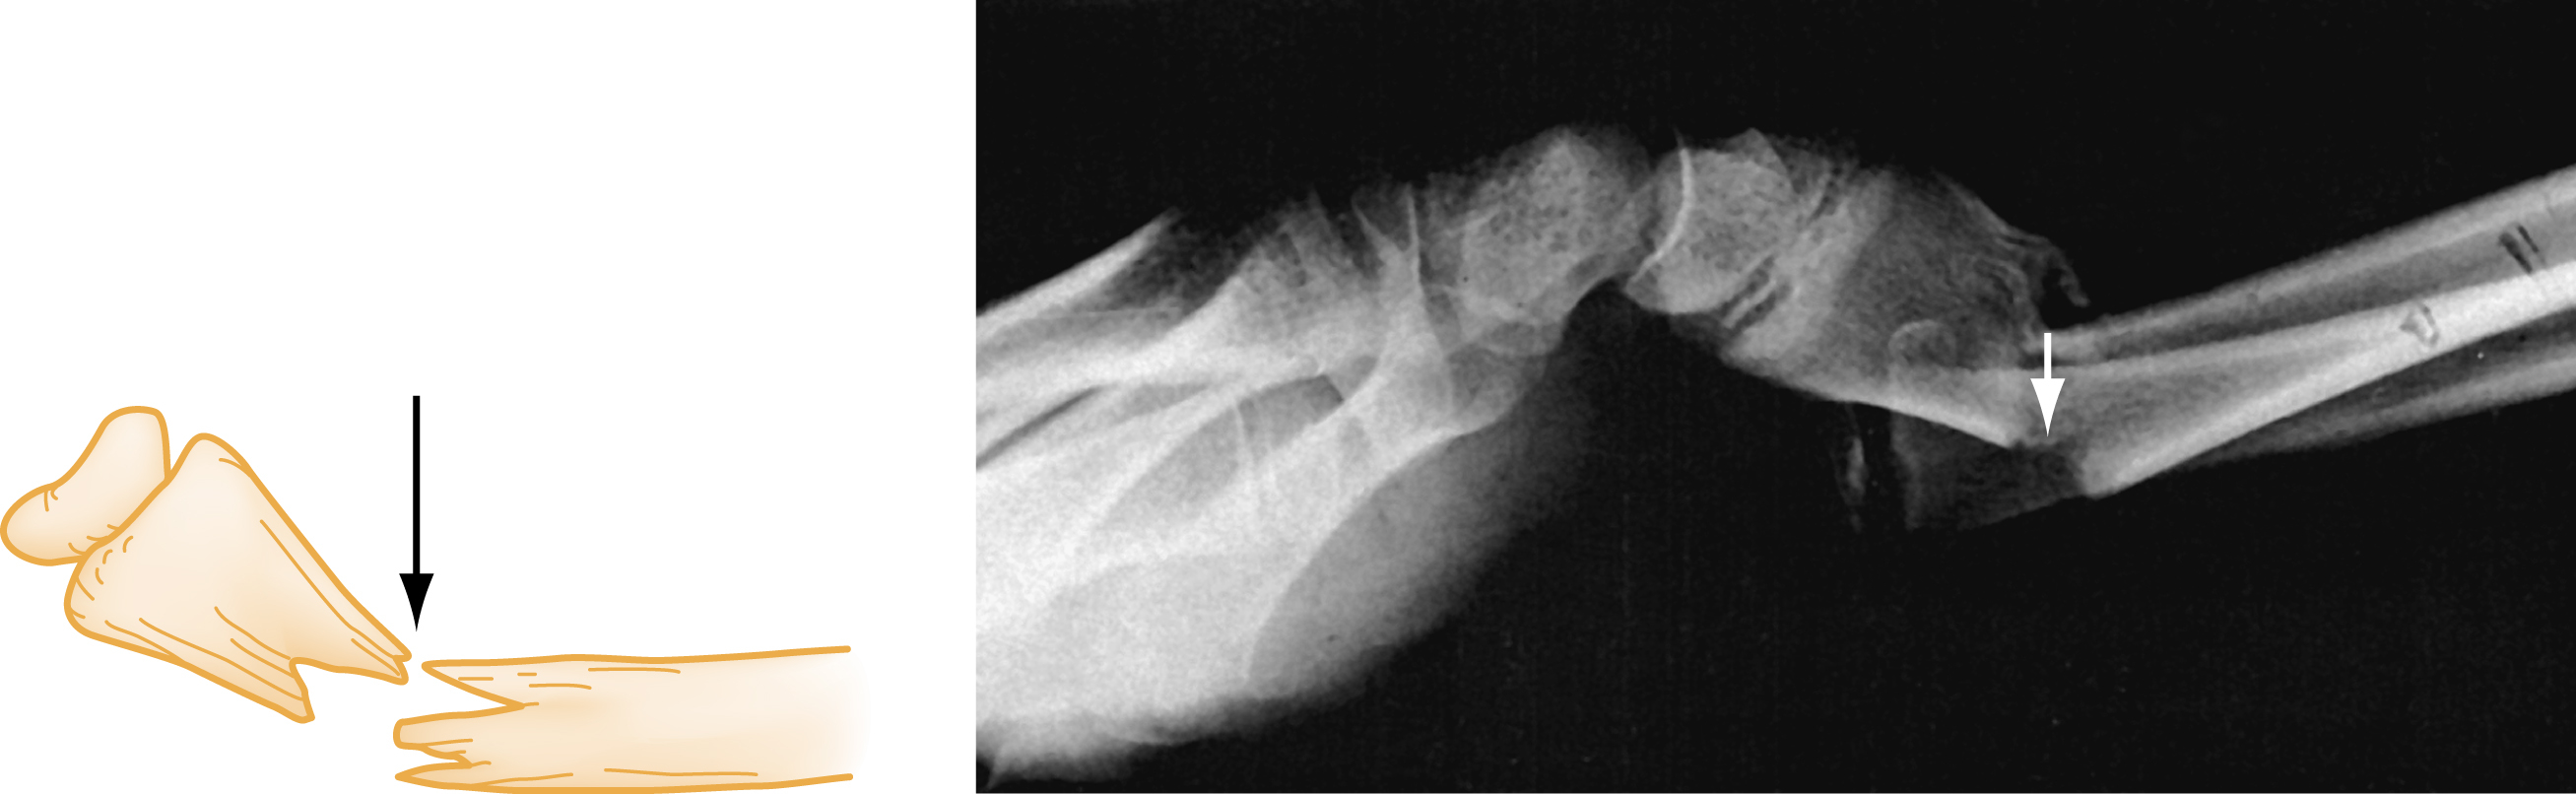

An additional modifier describes the direction of the fracture line in relation to the long axis of the bone in question. A transverse fracture occurs at a right angle to the long axis of the bone ( Fig. 41.1A ) whereas an oblique fracture runs oblique to the long axis of the bone (see Fig. 41.1B ). A spiral fracture results from a rotational force, a torque, and encircles the shaft of a long bone in a spiral fashion (see Fig. 41C ). The terms oblique and spiral are sometimes confused but can be important since the latter may have significance when child abuse is being considered as a mechanism of injury. A fracture with more than two fragments is termed comminuted (see Fig. 41.1D ).

Types of Fractures.

(A) Transverse. (B) Oblique. (C) Spiral. (D) Comminuted.

The term avulsion fracture refers to a bone fragment that is pulled away from its normal position by the forceful contraction of a muscle ( Fig. 41.5A ) or the resistance of a tendon or ligament to a force in the opposite direction (see Fig. 41.5B ). The term impaction refers to the forceful collapse of one fragment of bone into or onto another. In the proximal humerus, this collapse typically occurs in a telescoping manner, particularly in older patients, whose bones are osteoporotic and brittle. In the tibial plateau, impaction occurs frequently in the form of a depression ( Fig. 41.6A and B ) and, in the vertebral bodies, impaction frequently occurs in the form of compression resulting in a significant loss of bone height in some cases (see Fig. 41.6C ).

Avulsion Fractures.

(A) Musculotendinous avulsions of small bone fragments from the head of the humerus (arrows) . (B) Extensor tendon avulsion of bone from the base of the middle phalanx (arrow) .

(A and B) Tibial plateau fracture. (C) Vertebral body compression fracture (arrows) .